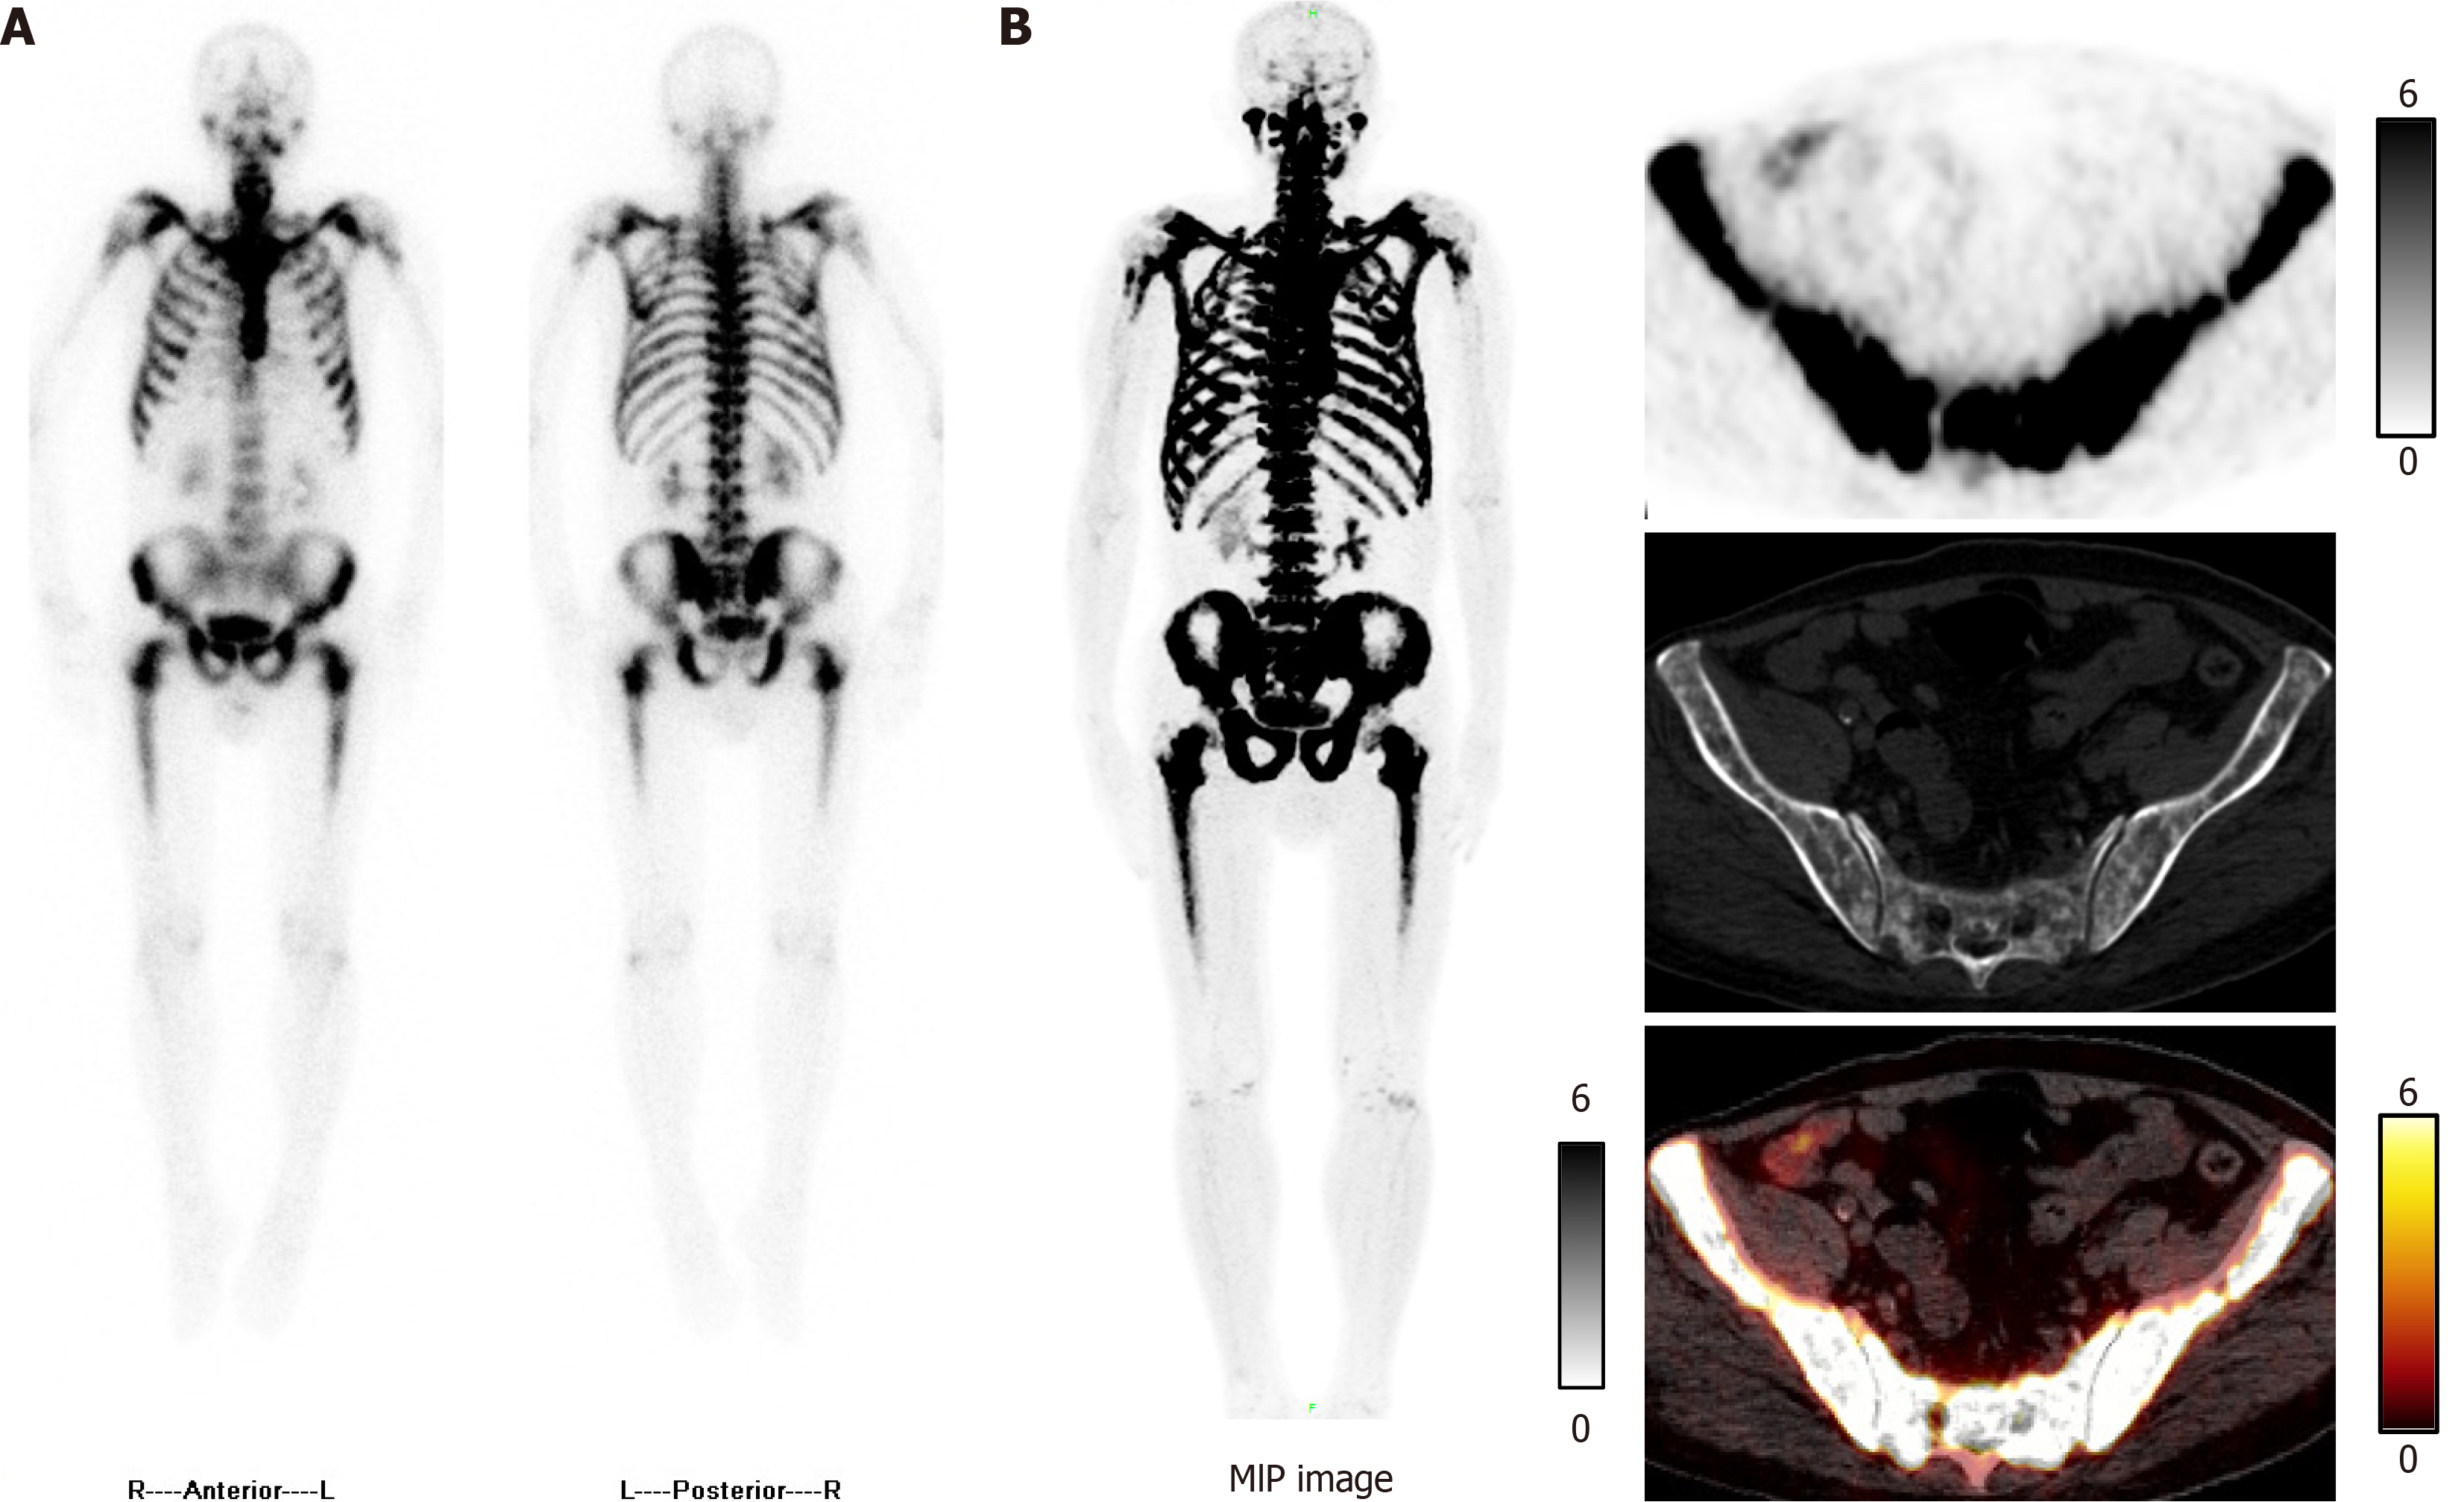

Figure 1 Technetium-99m methylene diphosphonate single-photon emission computed tomography and fluorine-18 sodium fluoride positron emission tomography/computed tomography images.

A: Whole-body bone scan showed diffuse increased technetium-99m methylene diphosphonate uptake throughout the skeleton; B: Symmetrical diffuse fluorine-18 sodium fluoride uptake was observed in the ribs, vertebrae, pelvis, and both femora. MIP: Maximum intensity projection.